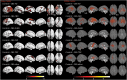

Figure 3. FDG-PET Across CBS Pathology Categories

Panels A–E show Z scores, relative to a normative database, of pons intensity normalized FDG-PET scans for each individual displayed on stereotactic surface projections using Cortex ID (GE Healthcare, Waukesha, WI). Red color indicates greater hypometabolism. AD = Alzheimer disease; CBD = corticobasal degeneration; CBS = corticobasal syndrome; DLBD = diffuse Lewy body dementia; FDG = 18F fluorodeoxyglucose; PSP = progressive supranuclear palsy; TDP = TAR DNA-binding protein 43.